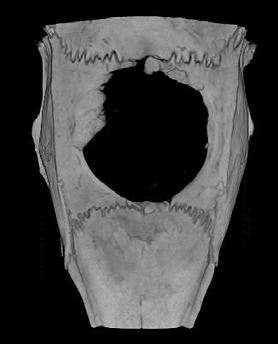

Researchers at City University of Hong Kong have developed a new, non-invasive imaging approach to examine the remains of beached marine mammals, like whales and dolphins. The approach, called virtopsy, was described in the journal Frontiers in Marine Science and can be used to determine the cause of death. It can also gather useful information about the animal before it died, such as its general health, as well as if it suffered human impacts, such as vessel collision or marine pollution.

Virtopsy uses modern imaging techniques to examine dead marine mammal remains. It is performed before conventional necropsy, the animal equivalent of human body-opening autopsies, or can even replace it in some cases.

“Virtopsy appears to be more accurate, time-saving and non-invasive compared to conventional necropsy, with less risk of

disease contraction for veterinarians and human rescuers,” says CityU radiological clinician Brian Chin-wing Kot.

In Hong Kong, marine mammal remains are often found badly decomposed on beaches, making conventional necropsies very difficult. Virtopsies provide an effective alternative to examine external and internal structures.

Kot and his team have performed virtopsies on more than 200 beached marine mammals using post-mortem computed tomography (PMCT) and post-mortem magnetic resonance imaging (PMMRI). The work shows that PMCT identifies bone lesions, foreign bodies, pathological gas formation and organ trauma better than conventional necropsy. PMMRI is

better at identifying soft tissue injury, organ trauma and non-traumatic pathology.

The team also found that PMMRI provides more information on decomposed brains than PMCT. Additionally, it should be used in conjunction with PMCT to detect soft tissue lesions and brain pathologies, as PMMRI alone is more prone to showing unwanted artefacts from gas and foreign bodies.